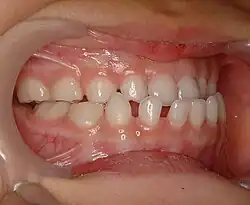

Ортогнатический прикус

Прикус, при котором верхние фронтальные зубы на одну треть длины перекрывают коронки нижних зубов[2].